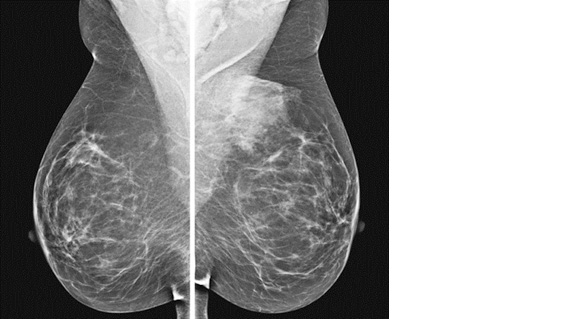

20대 이후에 발달한 여성형유방

사춘기 때에는 없었던 여성형유방이 한쪽 또는 양쪽 유방에서 발달할 수 있습니다. 간기능 이상, 콩팥기능 이상, 호르몬이상 등 전신질환의 한 증상으로 나타날 수 있으나 대부분은 특별한 원인 없이 젖샘조직이 발달하여 생기는 형태입니다. 이런 분들 중에는 드물지만 유방암이 있을 수도 있으므로 정밀검사를 해야 합니다.